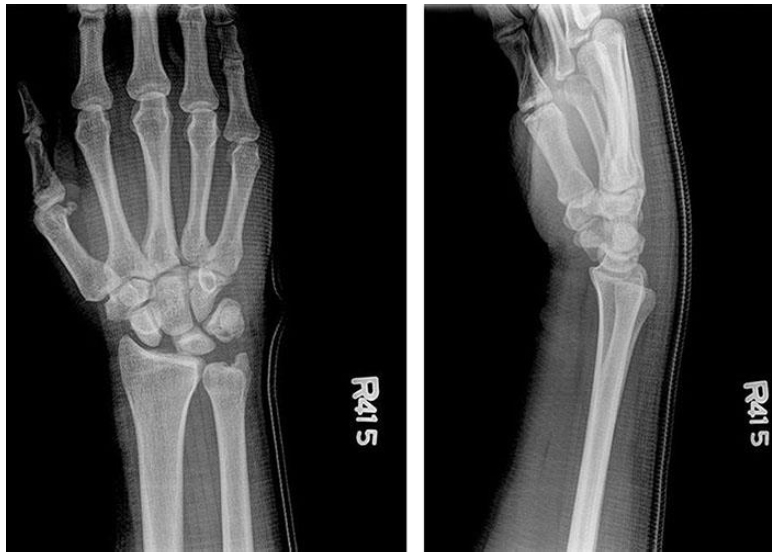

A 36-year-old man comes to the office because of a 2-week history of pain of the right wrist after a fall on his outstretched hand. X-ray studies are shown. If this injury is left untreated, which of the following joint surfaces is most likely to develop arthritis first?

The correct response is Option D.

The most likely joint surface to develop arthritis is the radioscaphoid joint. This patient shows evidence of scapholunate ligament tear. There is evidence of widening of the scapholunate interval and increase in the scapholunate angle.

The scapholunate angle is calculated by measuring the angle between a line drawn perpendicular to the distal surface of the lunate and along the axis of the scaphoid on the lateral view. The normal scapholunate angle varies from 30 to 60 degrees. A tear in the scapholunate ligament results in volar flexion of the scaphoid bone and dorsiflexion of the lunate, with a resultant increase in the angle.

If a scapholunate ligament tear is left untreated, a degenerative pattern of changes result. This is known as scapholunate advanced collapse (SLAC) wrist. Over time there is separation of the scaphoid and lunate bones and descent of the capitate into the intervening space.

With scapholunate ligament tears, arthritis occurs in a predictable sequence. This initially begins in the radioscaphoid joint, followed by the scaphocapitate joint and the capitolunate joint. The radiolunate joint is typically spared until advanced stages. The lunotriquetral ligament is intact and arthritis does not occur in this area with SLAC wrist.